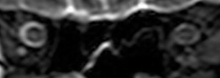

Intracranial pressure (ICP) needs to be directly measured before and after long duration flights to determine if microgravity causes the increased ICP. On the ground, lumbar puncture is the standard method of measuring cerebral spinal fluid pressure and ICP,[4][38] but this carries additional risk in-flight.[2] NASA is determining how to correlate ground-based MRI with inflight ultrasound[2] and other methods of measuring ICP in space is currently being investigated.[38]

The sixth case of visual changes of an ISS astronaut was reported after return to Earth from a 6-month mission. When he noticed that his far vision was clearer through his reading glasses. A fundus examination performed 3 weeks postflight documented a grade 1 nasal optic-disc edema in the right eye only. There was no evidence of disc edema in the left eye or choroidal folds in either eye (Figure 13). MRI of the brain and eyes days postflight revealed bilateral flattening of the posterior globe, right greater than left, and a mildly distended right optic nerve sheath. There was also evidence of optic-disc edema in the right eye. A fundus examination postflight revealed a "new onset" cotton-wool spot in the left eye. This was not observed in the fundus photographs taken 3 weeks postflight.[3]

The seventh case of visual changes associated with spaceflight is significant in that it was eventually treated postflight. Approximately 2 months into the ISS mission, the astronaut reported a progressive decrease in his near and far acuity in both eyes. The ISS cabin pressure, CO2 and O2 levels were reported to be within normal operating limits and the astronaut was not exposed to any toxic substances. He never experienced losses in subjective best-corrected acuity, color vision or stereopsis. A fundus examination revealed a grade 1 bilateral optic-disc edema and choroidal folds (Figure 15).[3]